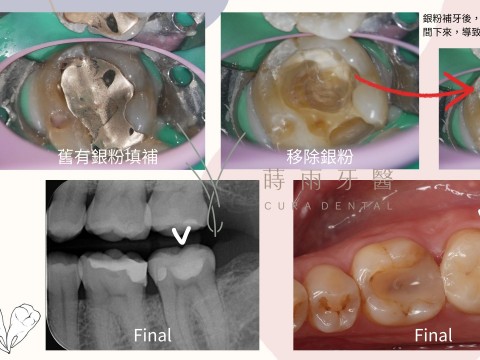

牙齒裂痕可大可小 - 小裂痕可能變成大麻煩

什麼是裂齒症:牙齒因瞬間過重或集中的咬合力而產生的裂痕,當裂痕延伸至牙髓腔並引起疼痛、敏感等症狀時,稱為裂齒症候群。 因為裂痕可能很細小,診斷上較困難,X光片難以顯示,所以常需輔以顯微鏡、染劑或牙裂檢測...